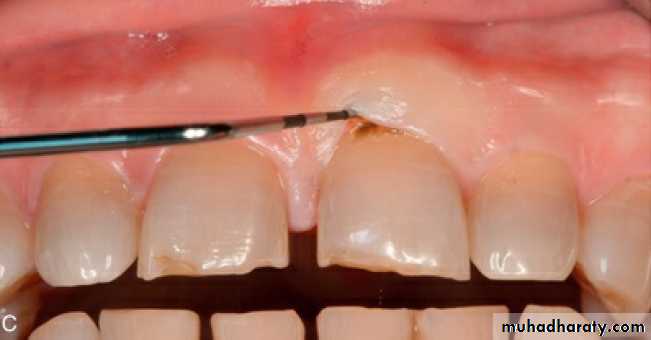

WASTING disease of teeth:

Gradual loss of tooth substance characterized by formation of smooth, polished surface

Erosion; wedge shaped depression in cervical area of facial tooth sur. E. caused by acidic food, acidic Salivary secretion, frectional action b/w soft & hard t.

Abrasion; caused by mechanical wear other than that of mastication started in Cementum due to clasp, tooth brushing

Attrition; occlusal wear due to functional contact with opposing teeth

Abfraction: occlusal loading surfaces causing tooth flexure and mechanical micro fracture the cervical area.